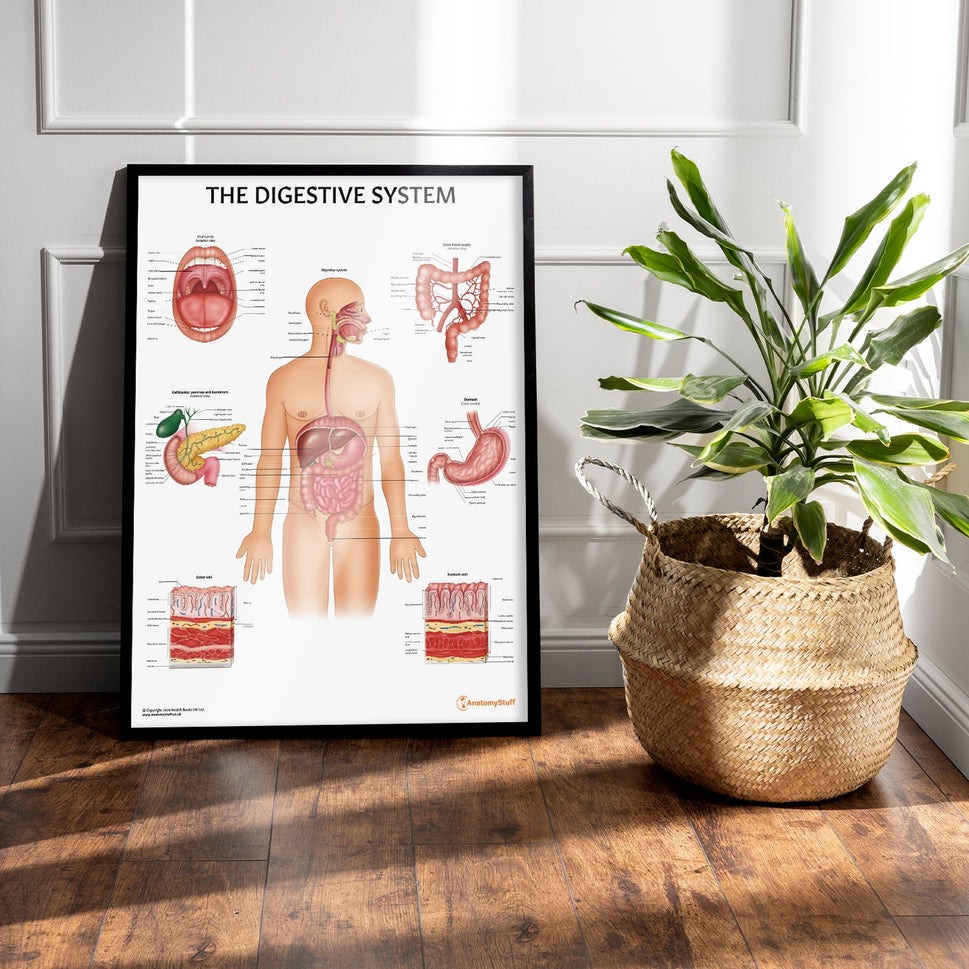

Enhance medical education with our collection of digestive system anatomical models including the stomach, liver, gallbladder, pancreas & colon models. Discover the anatomy of healthy organs as well as common gastrointestinal diseases such as stomach ulcers, gallstones and liver cirrhosis. Our digestive system anatomy posters are ideal for study and patient education.

At AnatomyStuff we stock a diverse range of digestive system anatomical models to suit your training needs. From budget models and affordable medical education posters to highly advanced 3D printed bowel models, you can transform medical training and patient education. As well as our own exclusive collection, we are proud resellers of 3B Scientific, Anatomy Lab, Denoyer-Geppert Science Company, ESP Models, Erler Zimmer and GPI Anatomicals. Explore our exclusive collection of digestive system anatomy charts, posters, fine art prints and digital anatomy study guides. Discover the anatomy of key organs like the liver, stomach, pancreas and bowel as well as the pathophysiology of common conditions like peptic ulcer disease, coeliac disease, IBD and much more. We have anatomy posters suitable for school children all the way up to medical degree level. From a liver anatomy poster to a digital study guide all about common GI disorders, find exactly what you need right here to enhance medical training and patient education.